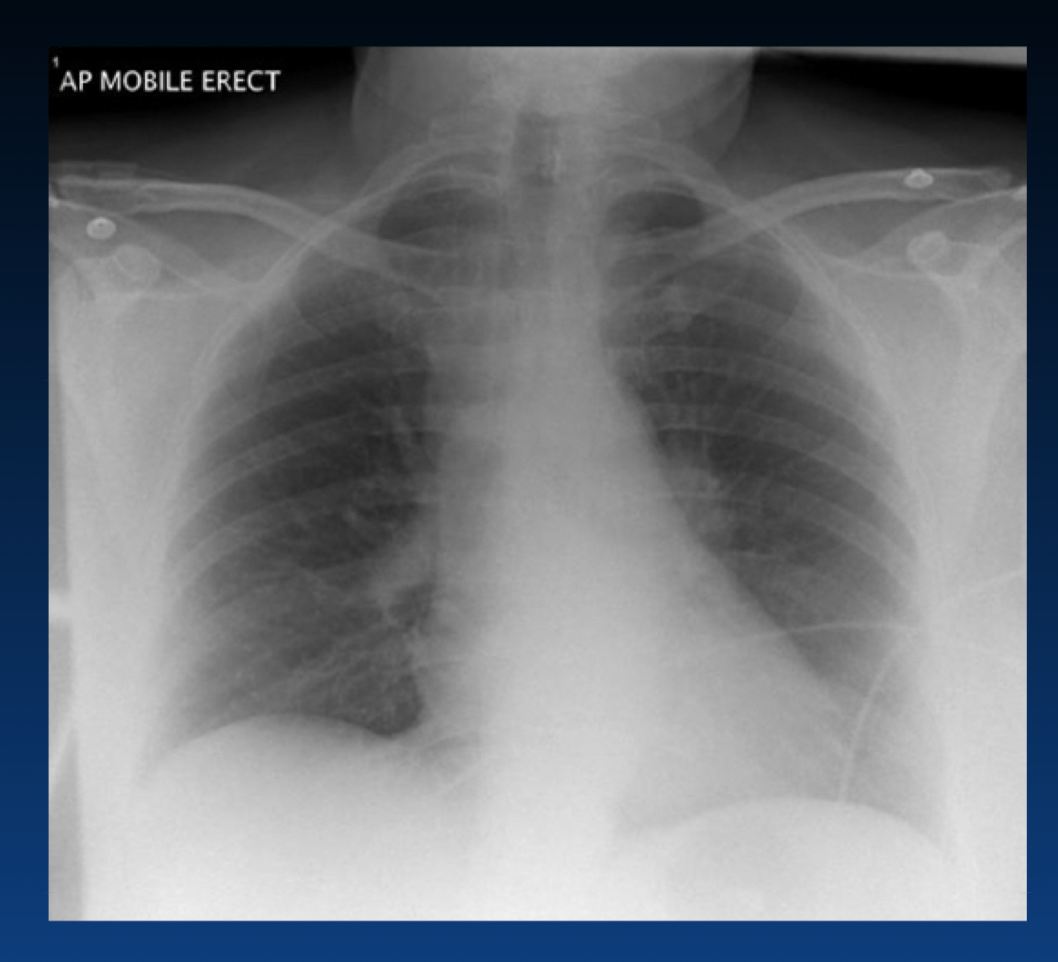

How is chest x-ray used in acute pulmonary embolism?

What are the features of right heart strain from pulmonary embolism?